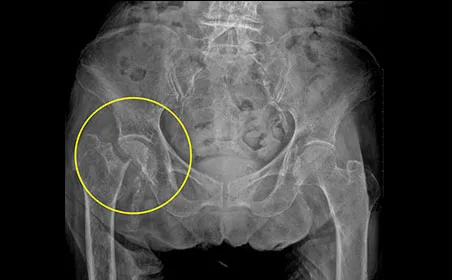

고관절은 특히 뼈 조직이 약해지는 60세 이후에 침대에서 미끄러지거나 넘어지는 등 사소한 충격에도 쉽게 손상되기 쉽습니다. 평균 수명이 증가함에 따라 고관절 골절의 빈도도 늘고 있습니다. 고관절 골절은 대퇴골의 목 부위가 골절되는 대퇴 경부 골절과 목 아래 부위가 골절되는 대퇴골간 골절로 나눌 수 있습니다. 노인에게는 잦은 낙상으로 인해 대퇴골간 골절이 더 흔하게 발생합니다.

대퇴골이 골절되면 심한 통증으로 인해 제대로 걷거나 앉을 수 없지만, 골절 정도에 따라 가벼운 통증만 느끼는 경우도 있습니다. 따라서 넘어진 후 고관절 부위가 붓거나 멍이 든다면 골절을 의심하고 바로 병원을 찾아 치료받는 것이 중요합니다.